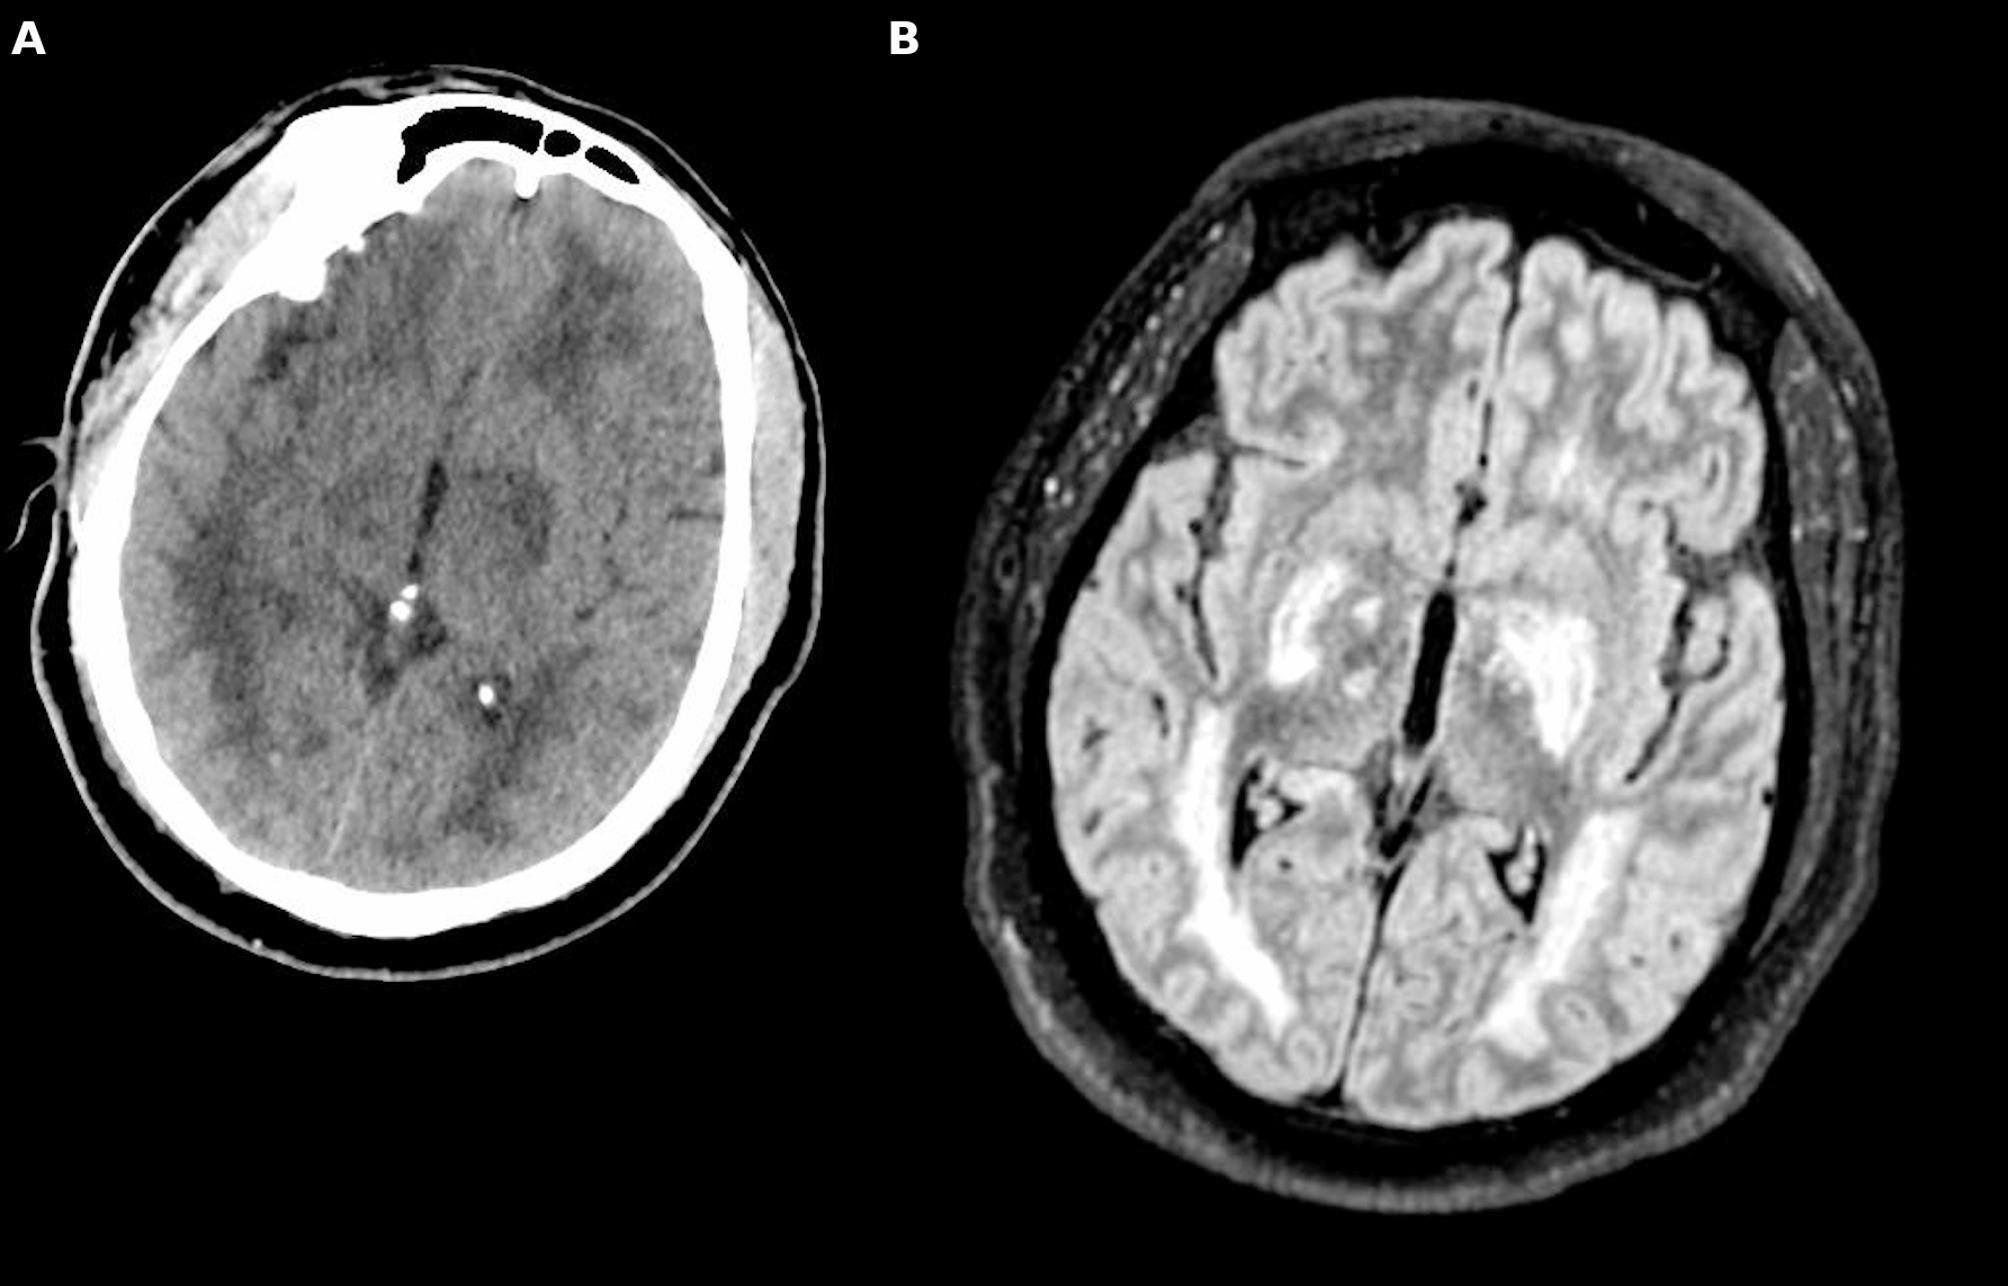

Severe malaria, caused by Plasmodium falciparum, poses a critical public health challenge, with cerebral malaria (CM) representing its most severe and life-threatening neurological manifestation. Defined by impaired consciousness (Glasgow Coma Score < 11) after the exclusion of other causes of encephalopathy, CM remains a critical condition with a mortality rate of 15-25% and long-term neurological sequelae in survivors. CM pathogenesis involves parasitized erythrocyte sequestration in cerebral microvasculature, immune hyperactivation, blood-brain barrier disruption, and cerebral edema, potentially leading to elevated intracranial pressure (ICP) and cerebral ischemia. These processes culminate in severe neurological injury, emphasizing the importance of ICP management in minimizing secondary brain damage. Neuromonitoring (NM) strategies, including invasive and non-invasive techniques, are critical yet underutilized in adults with CM due to limited evidence and logistical challenges. Treatment relies on antimalarial therapy, with intravenous artesunate as the first-line drug, supported by targeted interventions to manage seizures and systemic complications. Adjunctive therapies remain experimental, with no proven benefit in routine care. Emerging evidence from pediatric studies offers valuable insights, though significant gaps in adult-focused research persist. This review, which examines severe CM pathophysiology, clinical manifestations, and management, focusing on adult populations, underscores the need for tailored NM approaches, protocolized management strategies, and further investigation to improve outcomes in adults with CM, advocating for a multidisciplinary approach within the intensive care setting.